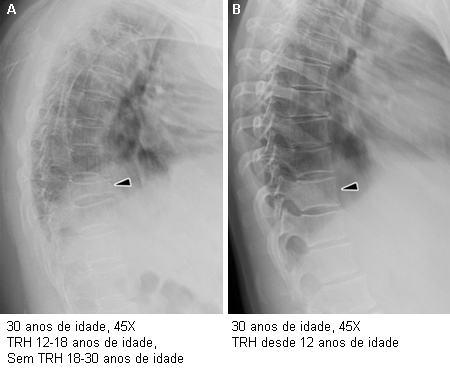

Importância da terapia estrogênica em mulheres adultas jovens com síndrome de Turner (ST): a imagem radiográfica na Figura A apresenta a T11 próxima de um colapso, osteoporose difusa e cifose dorsal em uma mulher com ST que interrompeu a terapia de reposição hormonal (TRH) aos 18 anos de idade. A Figura B mostra arquitetura vertebral e saúde óssea normais em outra mulher com ST, com 30 anos de idade, que tem feito uso da TRH consistentemente desde os 12.8 anos de idade

Do acervo pessoal de Carolyn Bondy, MS, MD (estudo do National Institutes of Health [NIH])